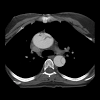

com.panorad.rfc.errad

Radiology Flashcards: ER was designed for radiology resident and emergency radiology fellowship education. Physicians, residents, medical students, and anyone interested in pursuing a career in medical imaging will also find this app useful.Radiology Flashcards: ER provides the user with 95 high quality interactive images including plain film, CT, and MRI. On the opposite side of the flashcard is the correct diagnosis followed by a brief fact that can be memorized.Keep track of the items you missed, optimize your study time, and focus on high-yield clinically relevant concepts.In collaboration with Hawki, Inc, makers of Radiology Flashcards for iOS.